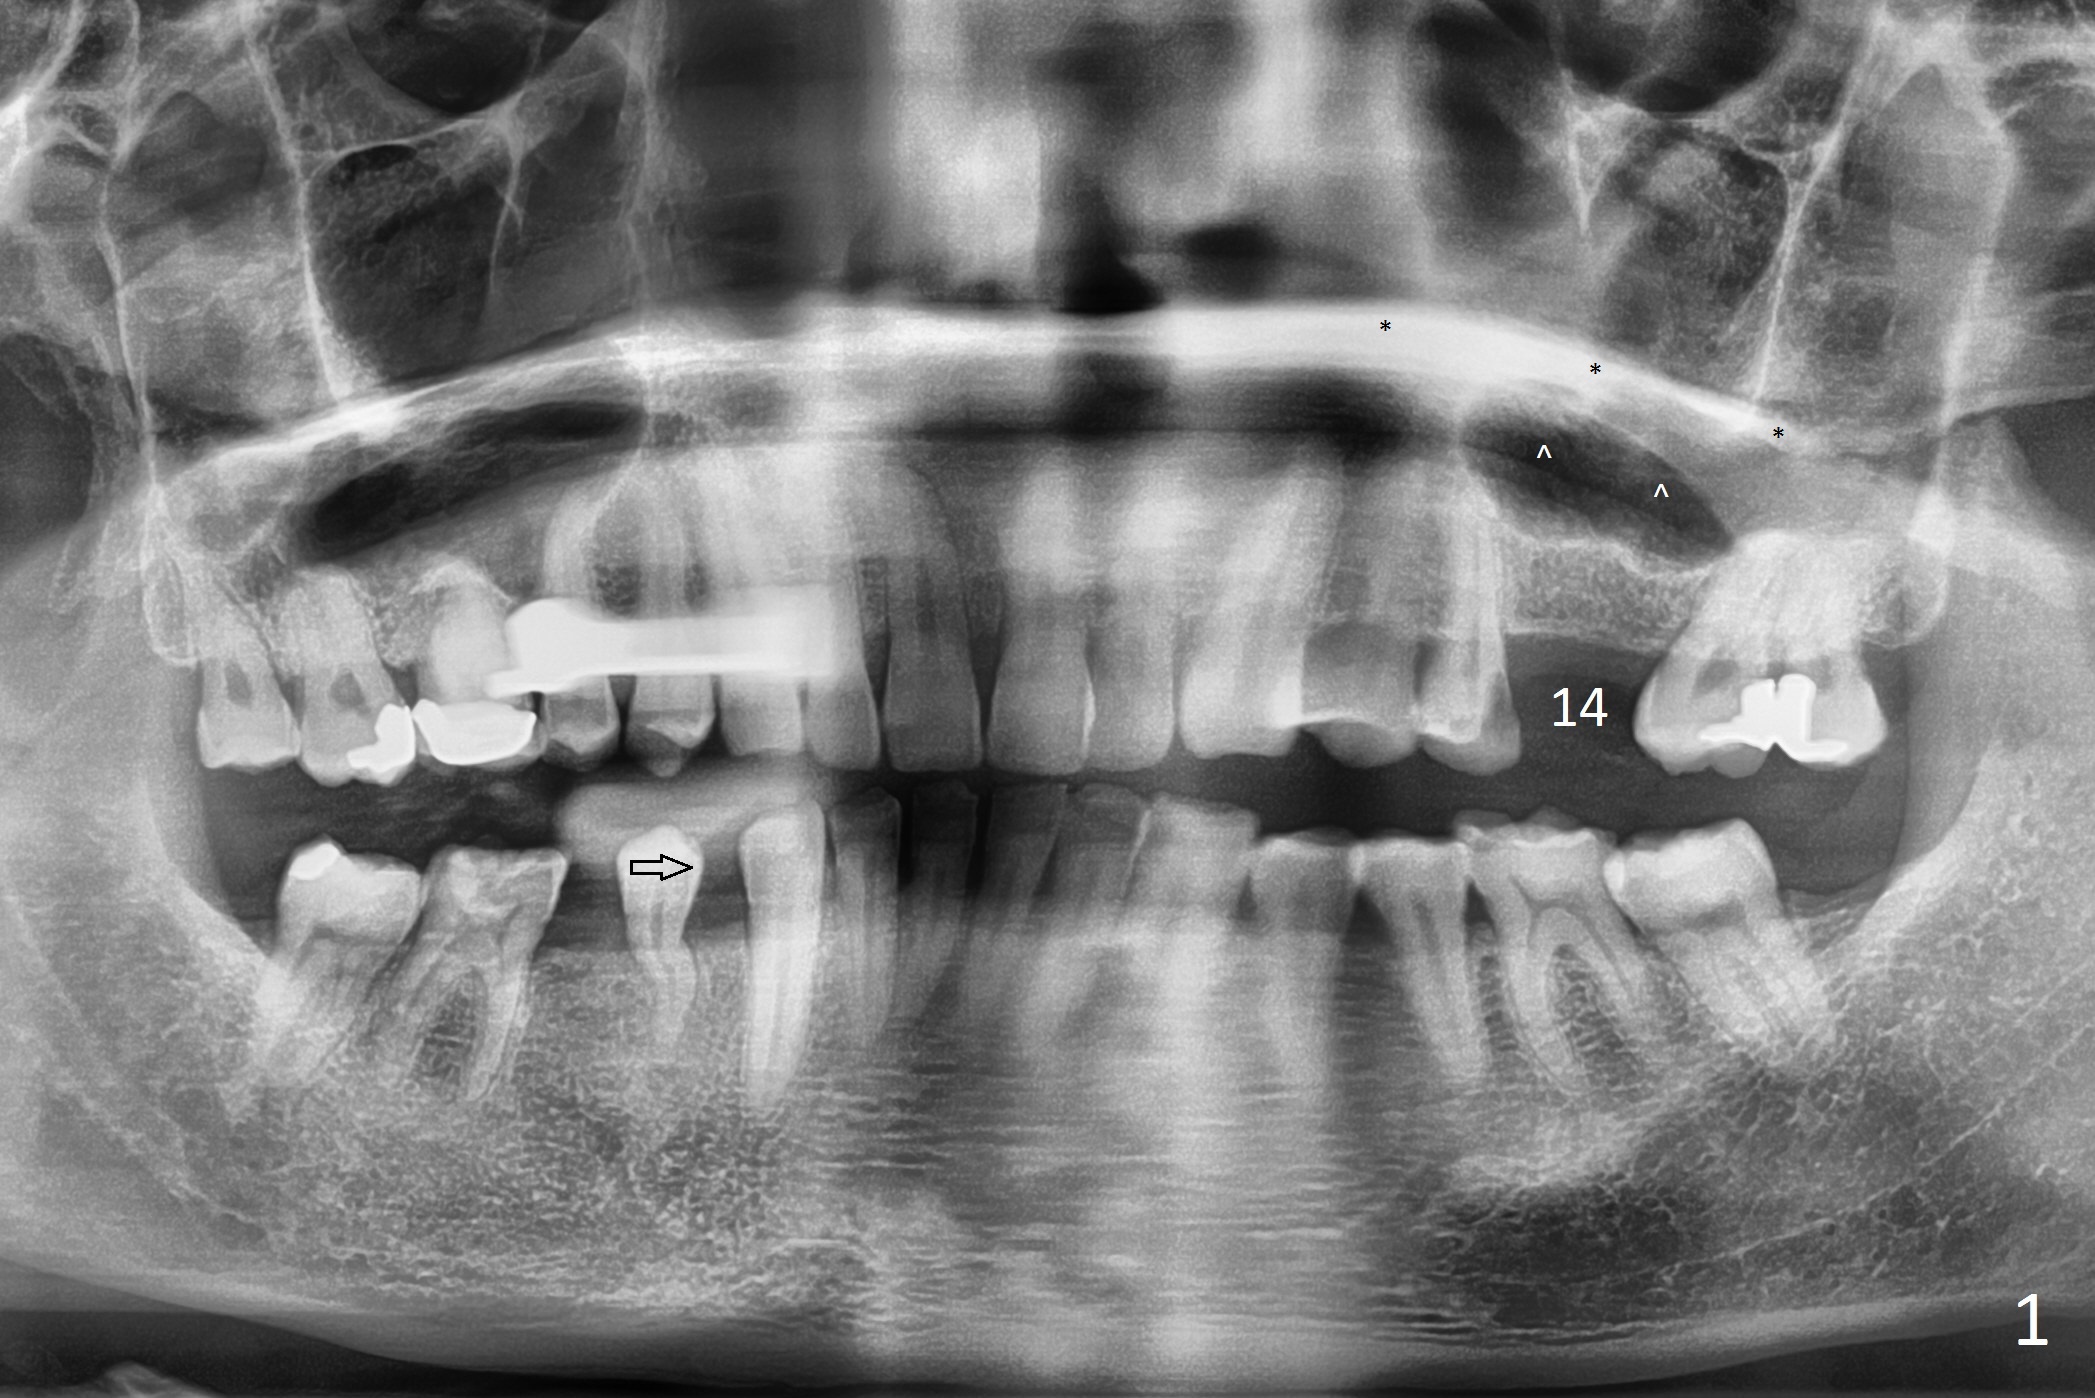

A 47-year-old man agrees implant at #14 (Fig.1).  He worries about the bone height.  There appear to be 2 layers of the sinus floor (Fig.1,2 (arrowheads: upper one)).  The horizontal plate of the palate is indicated by *.  An IBS implant will be placed between the 2 layers of the sinus floor as shown in Fig.3.  Osteotomy is initiated with Magic Split, followed by Magic Expanders (initial depth 9 mm gingival level) or Magic Lifter.  Before placing the implant, insert PRF and Allograft with a condenser with a stopper.